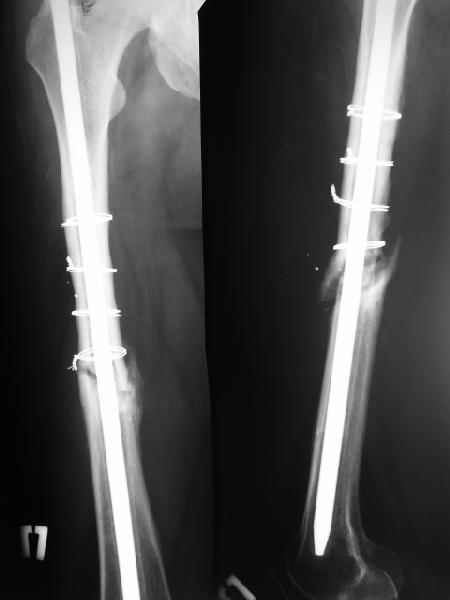

На данный момент правая голень срослась, больной активен в пределах постели. Второе(правое) бедро стабилизированное (рис. до и после). движения в коленном суставе: сгибательная контрактура правого коленного сустава 90, левого 145.

1) Мы бы не убирали проволоку, и вообще не вмешивались открыто на очаге - это ничего не даст, кроме ухудшения кровоснабжения концов отломков. Если просто закрыто перештифтовать при подобной картине, лучше с рассврливанием - это по нашему опыту дает сращение в 100%. В приложении пример - болезненное несращение более года, результат через полгода.

1

2